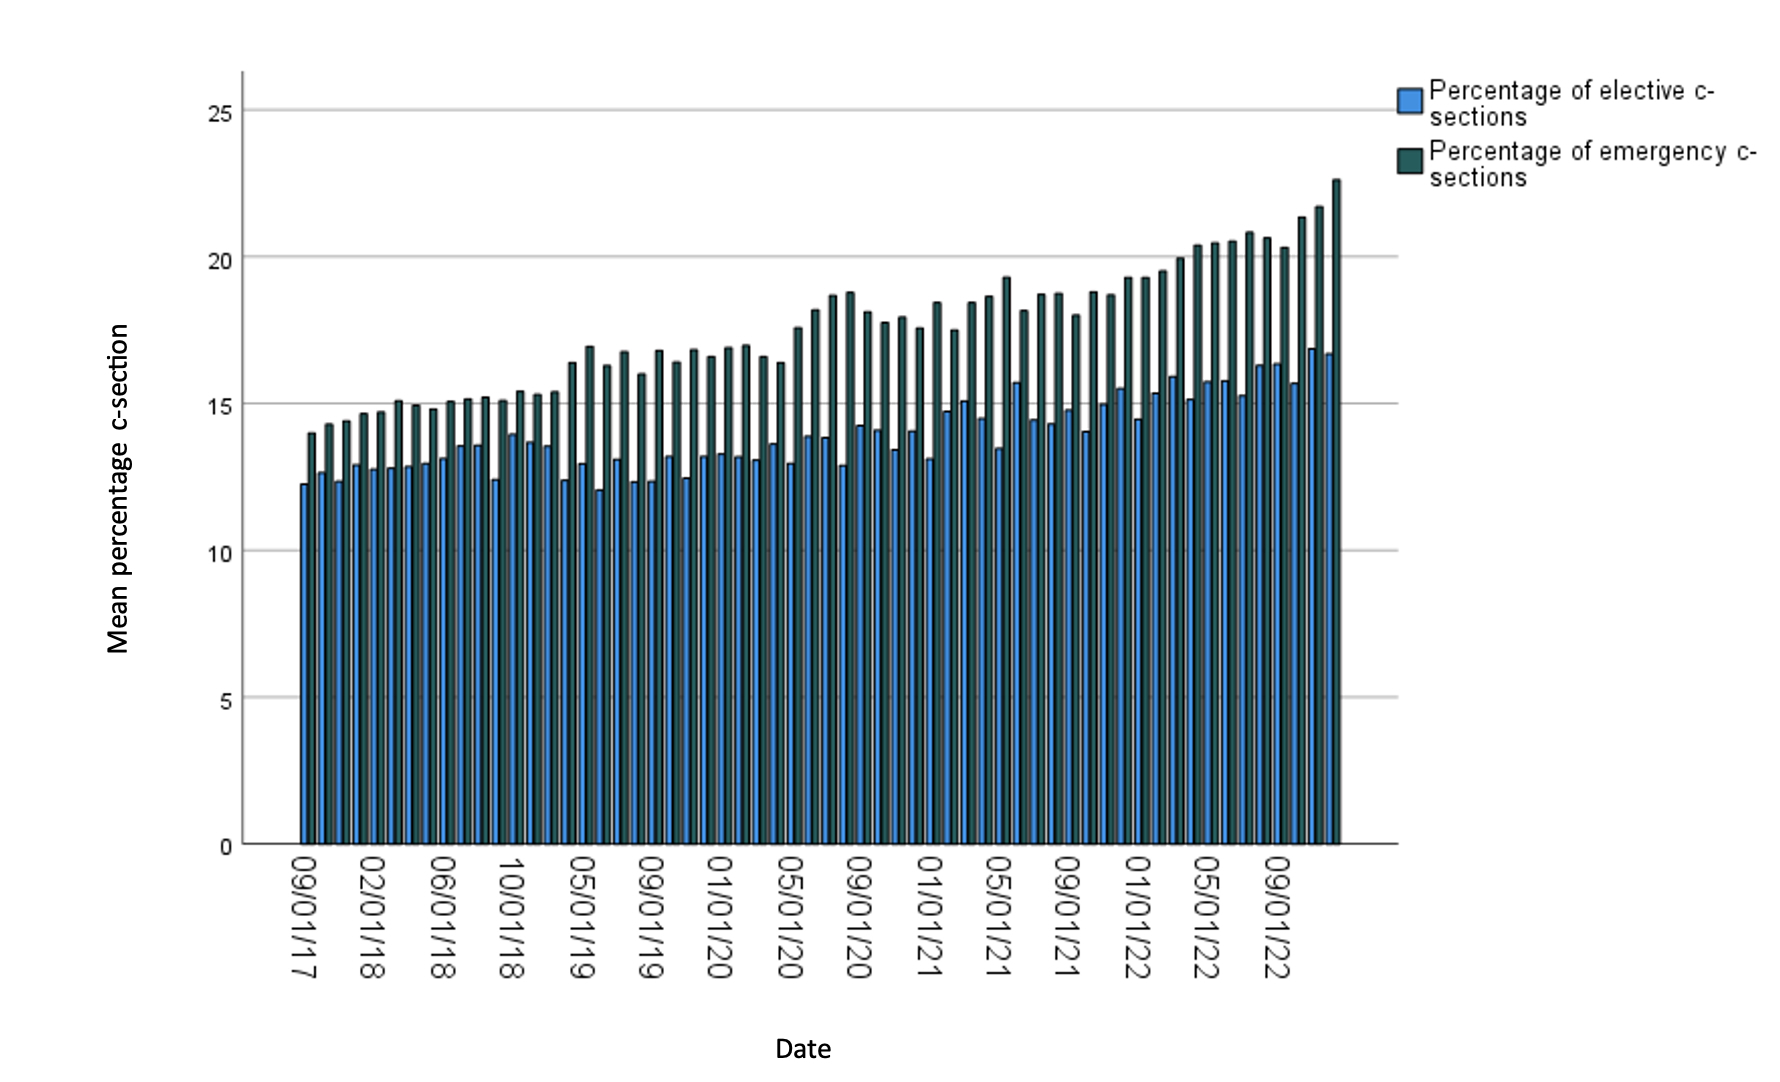

Investigating Rising Caesarean Sections in the National Health Service in England

This study investigates the relationship between named variables and elective and emergency caesarean section in England in the NHS.

Posted by buchanle on Tuesday, April 30th, 2024 in May 2024, C-sections, NHS, Pregnancy